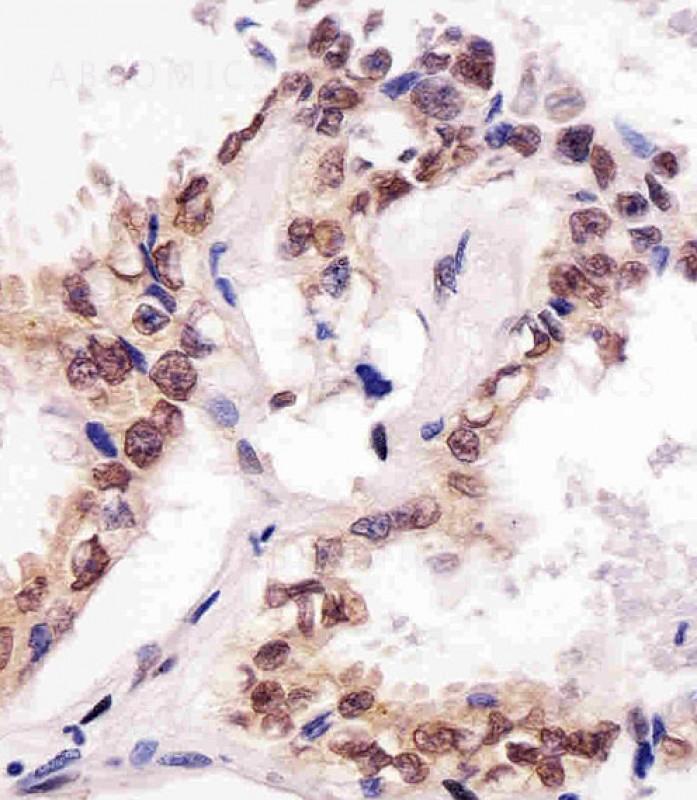

Figure 1: Staining of SUMO1 antibody (10-6519) in human lung adenocarcinoma tissue sections by Immunohistochemistry (IHC-P - paraformaldehyde-fixed, paraffin-embedded sections). Tissue was fixed with formaldehyde and blocked with 3% BSA for 0. 5 hour at room temperature; antigen retrieval was by heat mediation with a citrate buffer (pH6). Samples were incubated with primary antibody (1/25) for 1 hours at 37°C. A undiluted biotinylated goat polyvalent antibody was used as the secondary antibody.